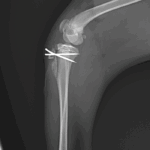

膝蓋骨内方脱臼G4

膝蓋骨内方脱臼G4により右後肢の負重が弱いという患者さんが紹介受診されました。膝蓋骨は大腿骨滑車から脱臼したままで大腿骨滑車内に誘導することができませんでした。大腿骨の変形などは幸い確認されませんでした。大腿骨滑車形成術、内側広筋の切離、脛骨粗面外側移行術、外側余剰関節包の切除によりアライメント手術を行いました。これから後療法も重要になります。